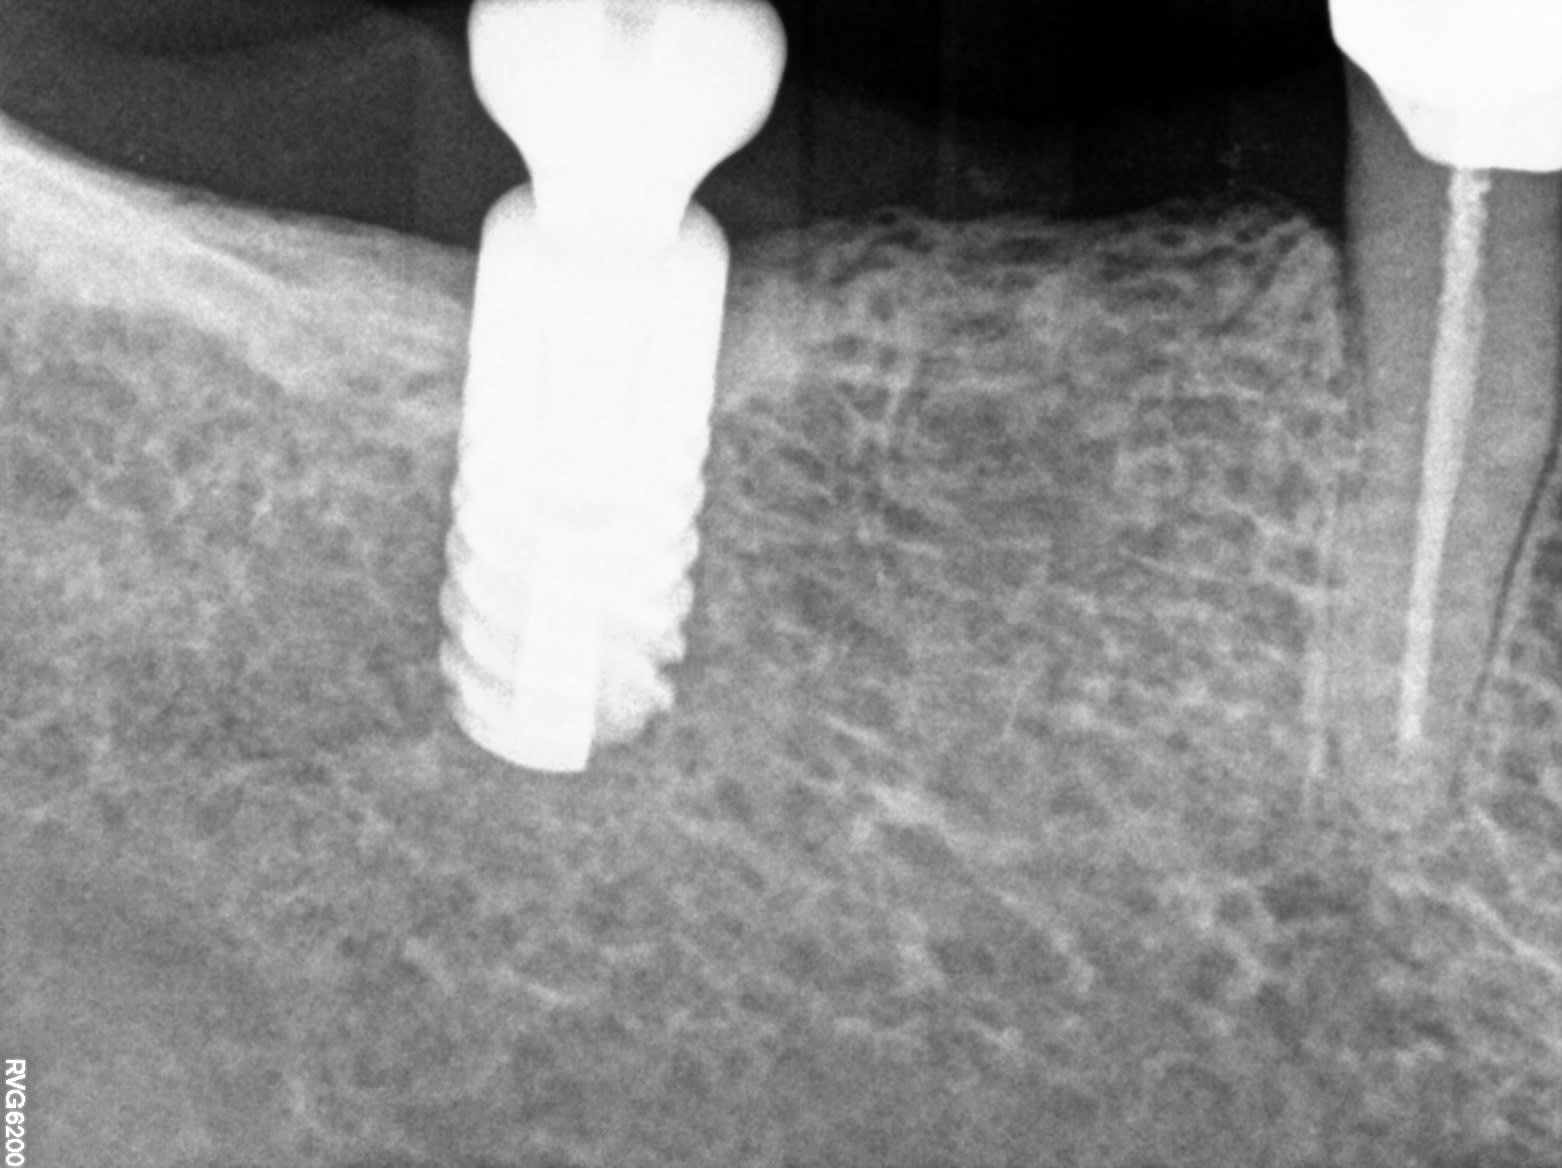

Pourriez vous m'aider dans l'identification de ces implants mandibulaires svp.

fastoche ID Cam de chez IDI

100% certain